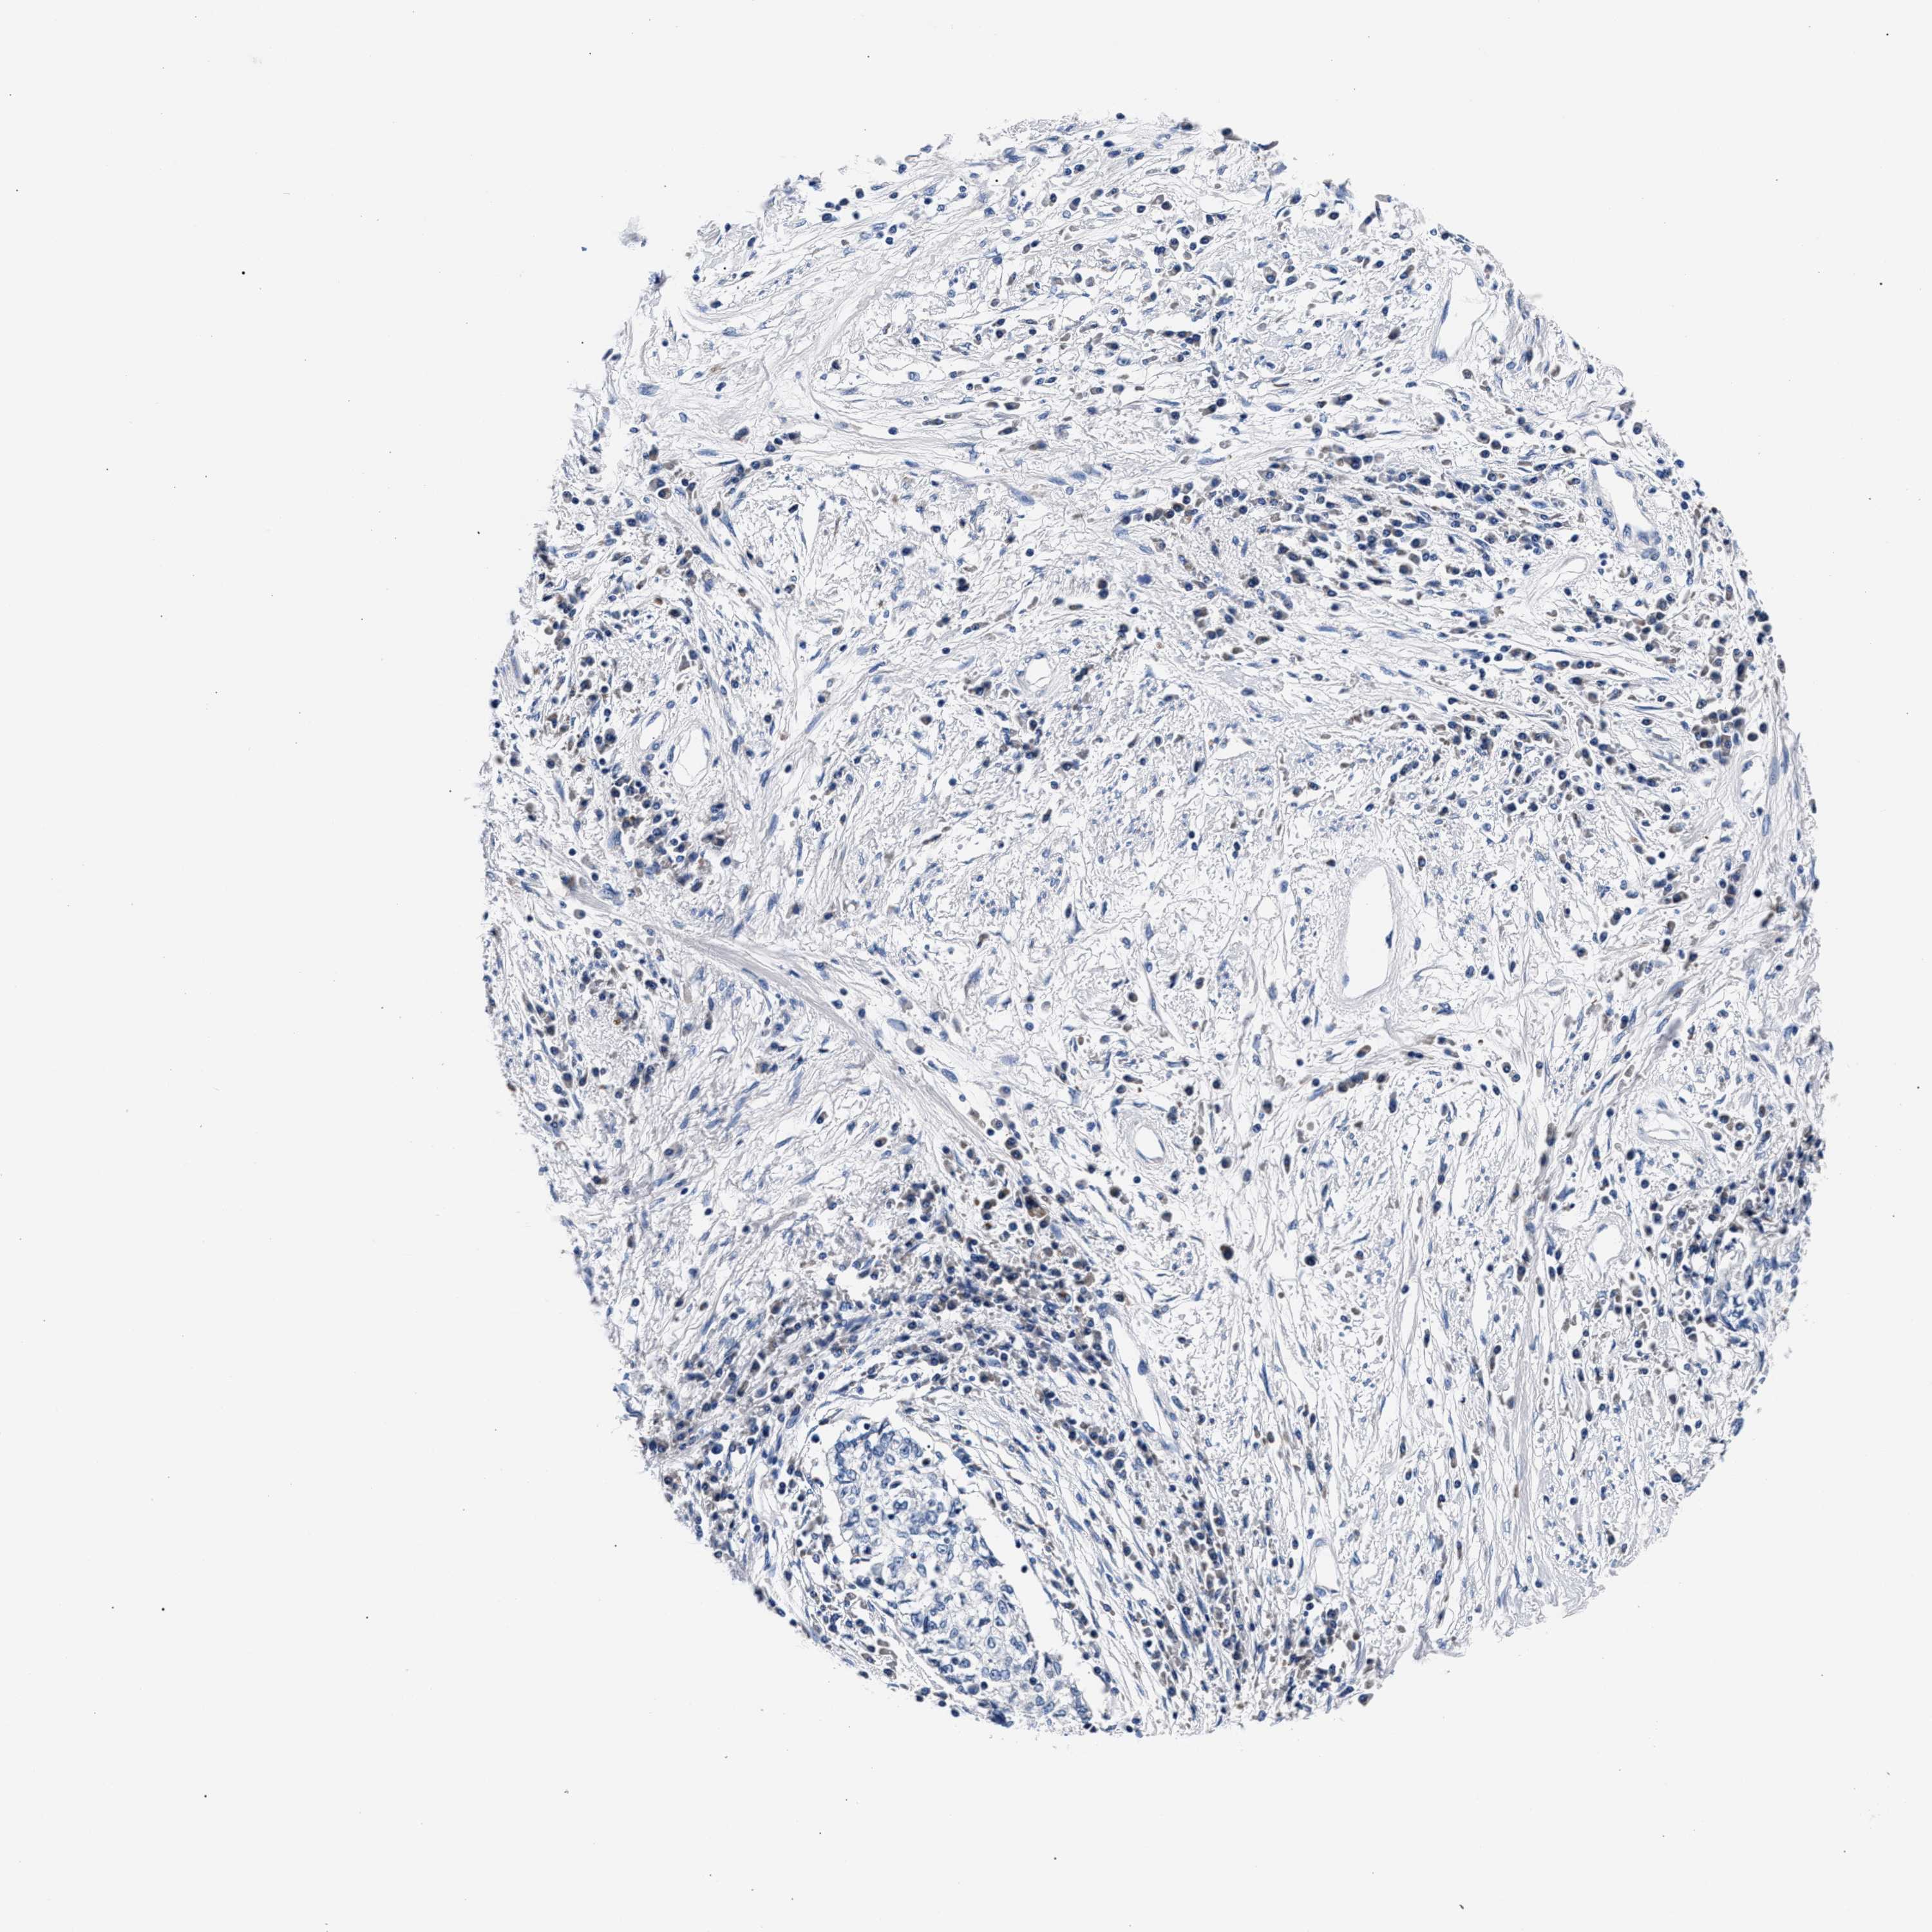

CERVICAL CANCER - Protein expressioni

A mouse-over function shows sample information and annotation data. Click on an image to view it in a full screen mode. Samples can be filtered based on level of antibody staining by selecting one or several of the following categories: high, medium, low and not detected. The assay and annotation is described here.

Note that samples used for immunohistochemistry by the Human Protein Atlas do not correspond to samples in the TCGA dataset.

Antibody stainingi

Antibody staining in the annotated cell types in the current human tissue is reported as not detected, low, medium, or high, based on conventional immunohistochemistry profiling in selected tissues. This score is based on the combination of the staining intensity and fraction of stained cells.

Each image is clickable and will lead to virtual microscopy that enables deeper exploration of all samples and also displays staining intensity scores, fraction scores and subcellular localization as well as patient and tissue information for each sample.

Antibody HPA020974

Staining

High

Medium

Low

Not detected

Intensity

Strong

Moderate

Weak

Negative

Quantity

>75%

75%-25%

<25%

None

Location

Nuclear

Cytoplasmic/membranous

Cytoplasmic/membranous,nuclear

Squamous cell carcinoma, NOS

Adenocarcinoma, NOS